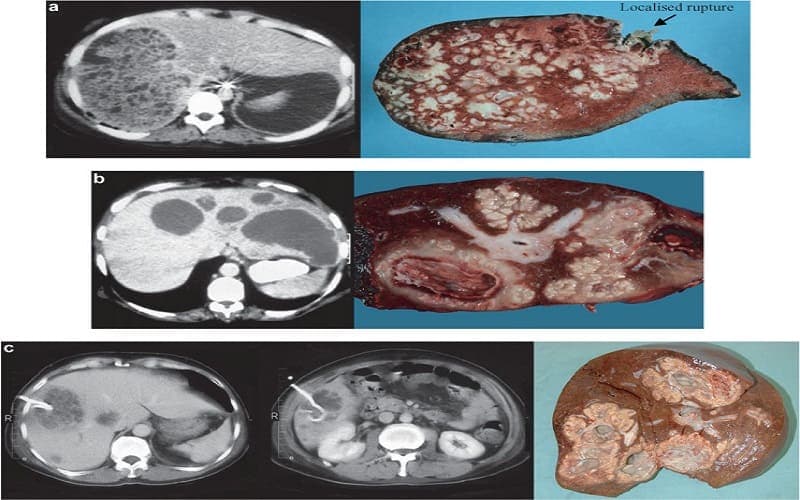

Hình ảnh cắt lớp của gan bị áp xe